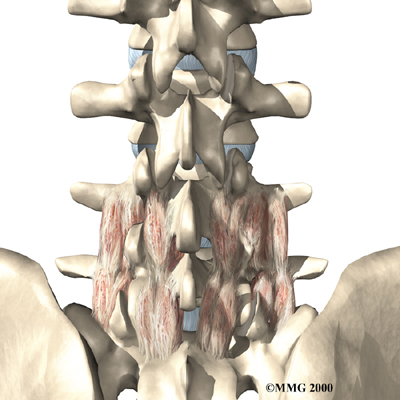

The human spine is formed by 24 spinal bones, called vertebrae. Vertebrae are stacked on top of one another to form the spinal column. The spinal column gives the body its form. It is the body's main upright support. The section of the spine in the lower back is known as the lumbar spine.

The lumbar spine is made up of the lower five vertebrae. Doctors often refer to these vertebrae as L1 to L5. These five vertebrae line up to give the low back a slight inward curve. The lowest vertebra of the lumbar spine, L5, connects to the top of the sacrum, a triangular bone at the base of the spine that fits between the two pelvic bones. Some people have an extra, or sixth, lumbar vertebra. This condition doesn't usually cause any particular problems.

The next part of our program will include a series of strengthening exercises for the abdominal and low back muscles. Working these core muscles helps our patients begin moving easier and lessens the chances of future pain and problems. Aerobic exercises such as walking or swimming are used for easing pain and improving endurance.